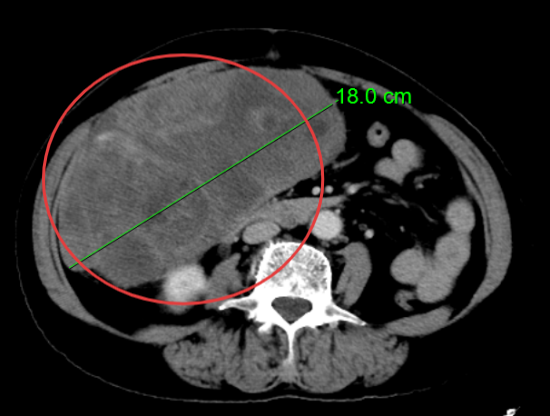

患者楊阿姨,因右下腹脹痛持續一月入院,經過詳細的腹部CT檢查,結果顯示其腹腔內存在一個巨大占位性病變,最大層面大小竟達到了驚人的18cm×10cm×14cm,腫瘤性質及來源尚不明確。面對如此龐大的腫瘤,手術難度可想而知。然而,楊阿姨的身體狀況更為復雜。術前檢查發現,她全心擴大,心臟彩超顯示三尖瓣大量反流,肺動脈高壓、二尖瓣大量反流,肺動脈瓣中量反流,并伴有心動過緩。這些心臟問題無疑為手術增添了巨大的風險。面對這樣心功能極差的患者,任何微小的失誤都可能導致不可挽回的后果。

CT報告結果